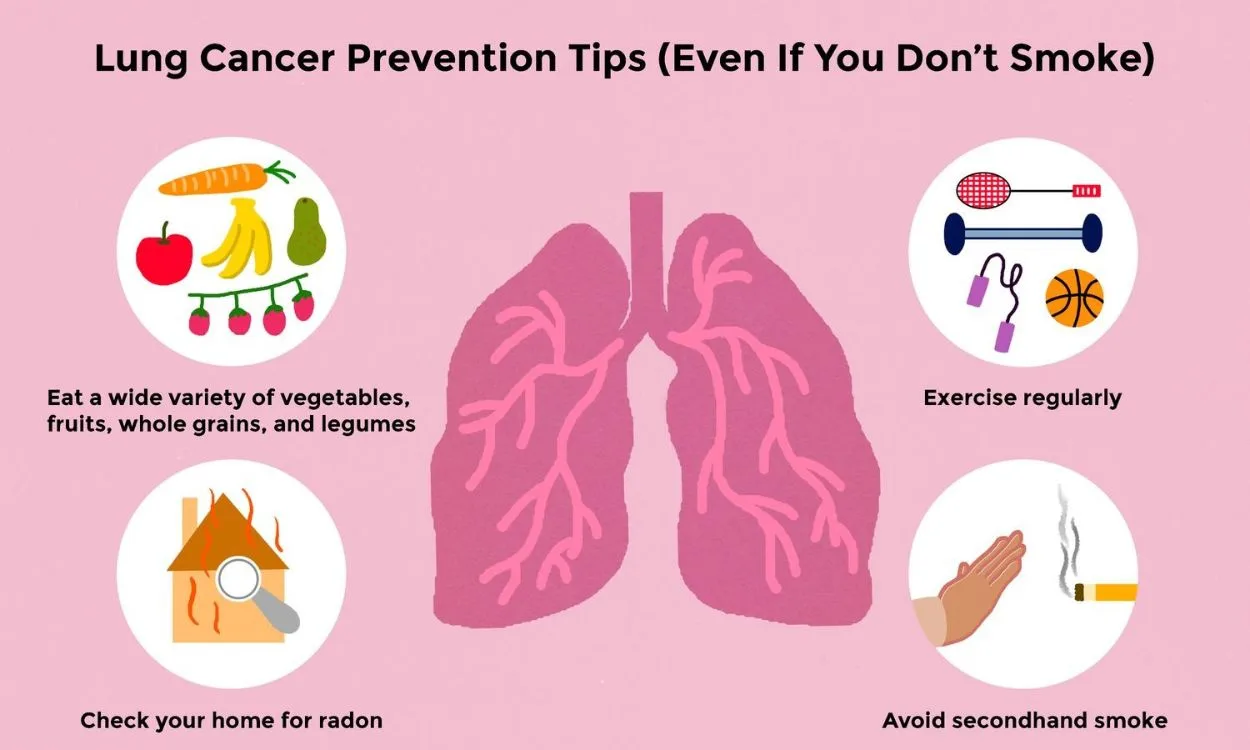

- Lung disease(52)

- Lung Health(52)